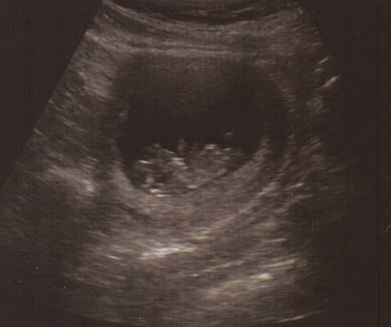

10 week, 1 day sono :-)

Had our 10 wk sono on monday. It was so exciting! Baby was moving its arms and feet. It still feels like I was looking at someone else's ultrasound since I can't feel it yet. So surreal.